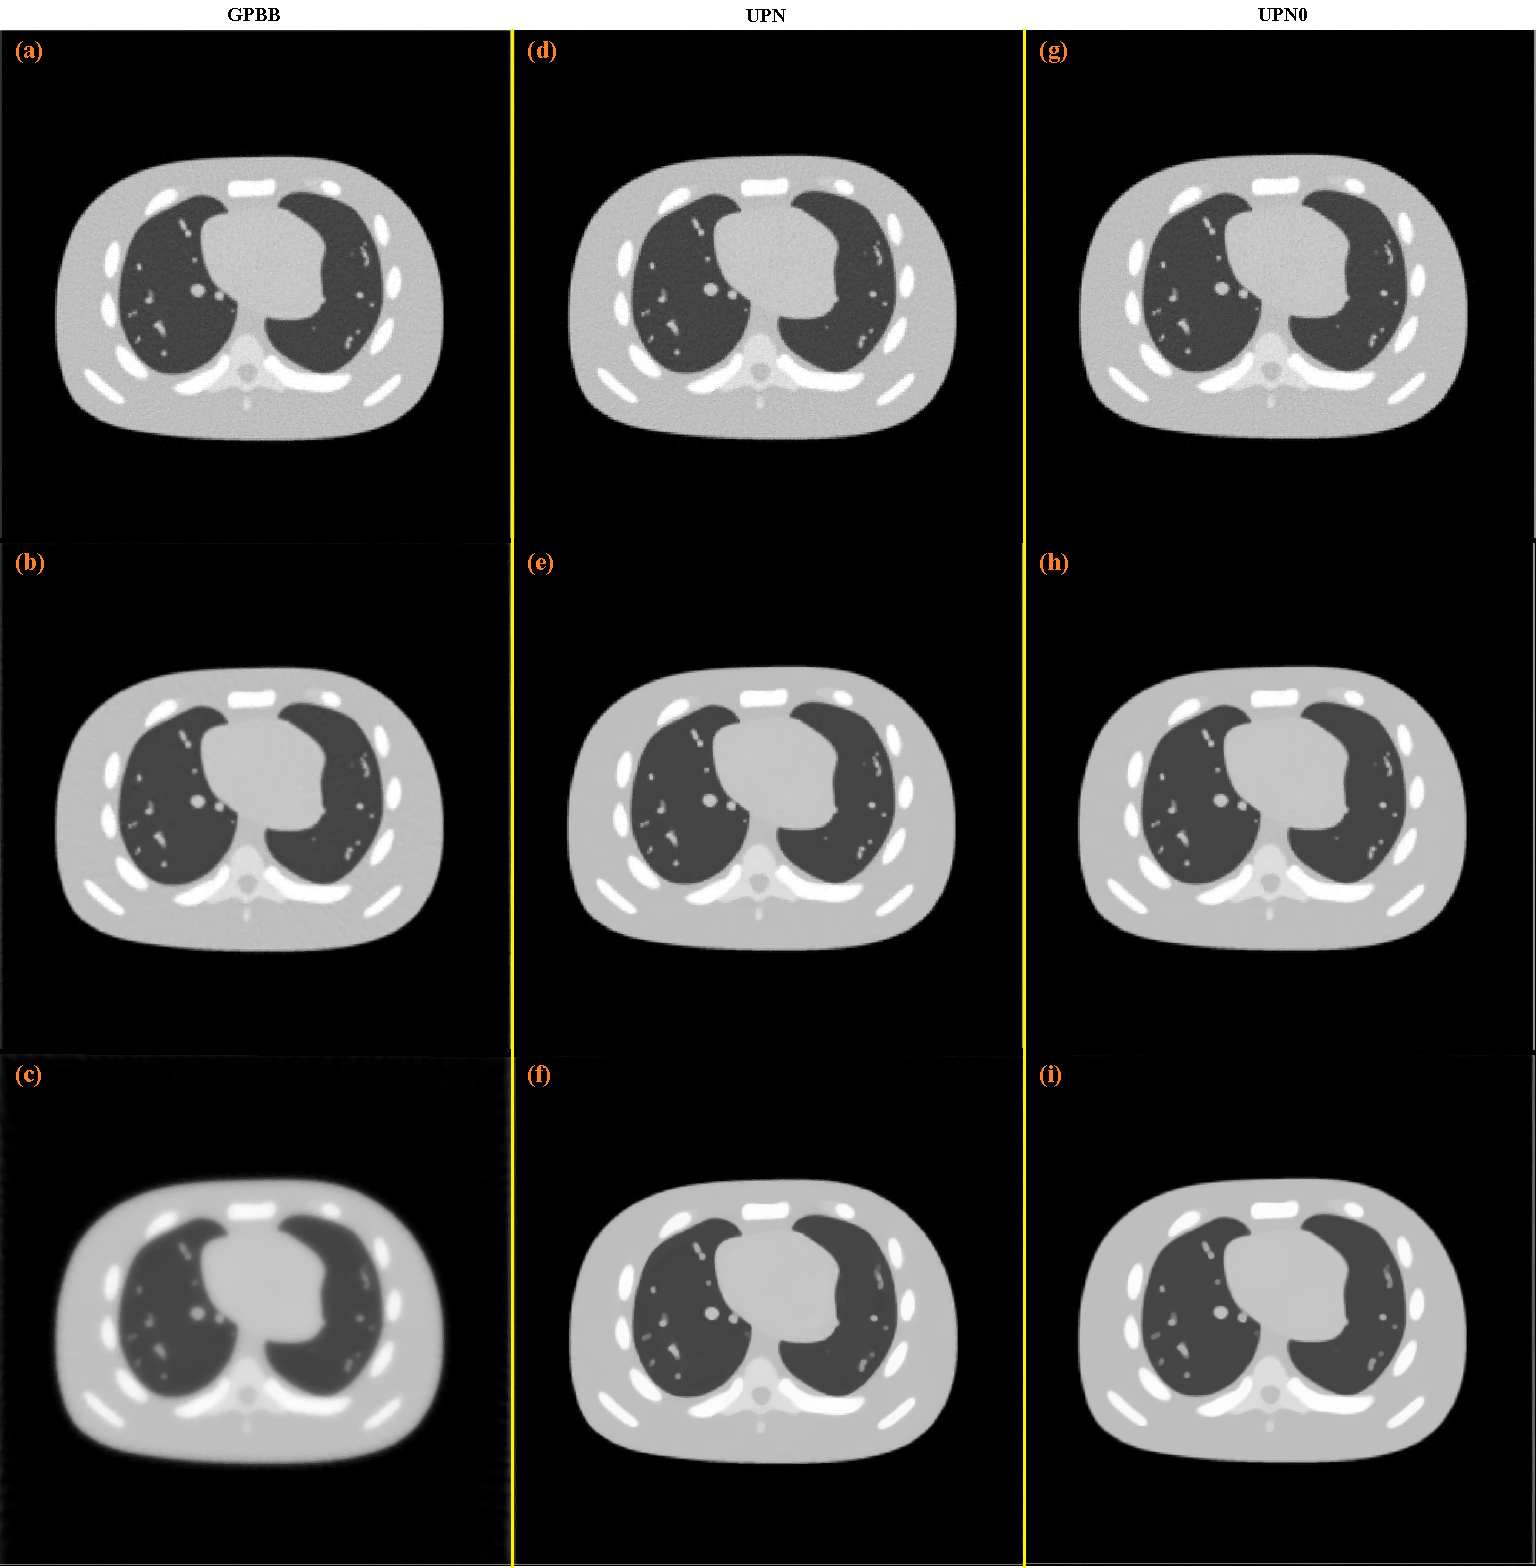

The reconstruction with the SbIR algorithm is shown in Fig. 2 (c), where in Fig. 2 (b) is shown the reconstruction obtained after the initialization step is applied. The reconstructions with the GPBB, UPN, UPN0 algorithms are shown in Fig. 3 when the regularization parameter α𝛼\alpha is 0.5, 5.0, or 50.0. In this example, the best reconstructions obtained with the GPBB, UPN, UPN0 algorithms are obtained when α=5.0𝛼5.0\alpha=5.0 (this means the middle row (b), (e) and (h) in Fig. 3).

Figure 3: (a), (b) and (c) are the results after 512 iterations for the GPBB method for α=0.5𝛼0.5\alpha=0.5, α=5.0𝛼5.0\alpha=5.0 and α=50.0𝛼50.0\alpha=50.0 respectively; (d), (e) and (f) are the results after 512 iterations for the UPN method for α=0.5𝛼0.5\alpha=0.5, α=5.0𝛼5.0\alpha=5.0 and α=50.0𝛼50.0\alpha=50.0 respectively; (g), (h) and (i) are the results after 512 iterations for the UPN0 method for α=0.5𝛼0.5\alpha=0.5, α=5.0𝛼5.0\alpha=5.0 and α=50.0𝛼50.0\alpha=50.0 respectively